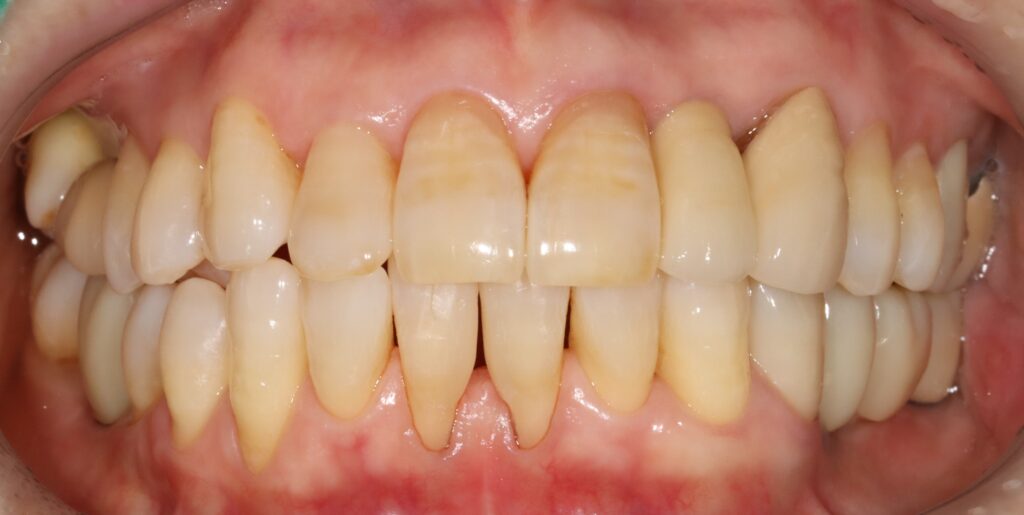

앞니의 색상을 결정하는 과정인데요.

앞니임플란트는 높은 난이도의 치료로

분류되는데 잇몸 라인과 치아의 색상·형태·배열까지

고려해야 하기 때문입니다.

자연치아와의 조화를 이루기 위해서는

의료진의 섬세한 판단과 풍부한 임상 경험이

필수적으로 을지로치과 선택 시에는

의료진의 경력과 앞니임플란트 시술 경험,

정품 재료 사용 여부, 합리적인 비용 체계 등을

종합적으로 확인하는 것이 바람직합니다.